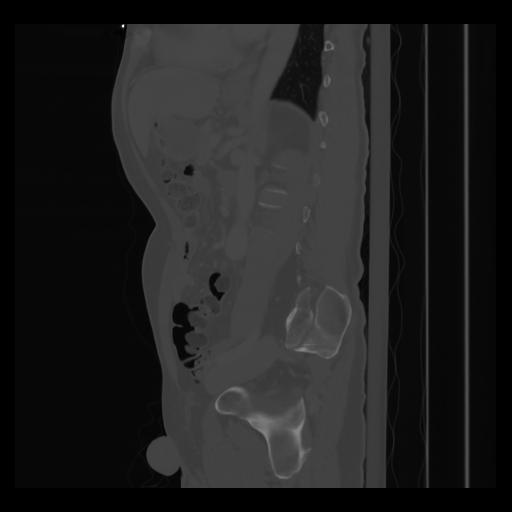

36 CUERPO,CE,Sagittal,3.000,CUERPO,Sagittal,